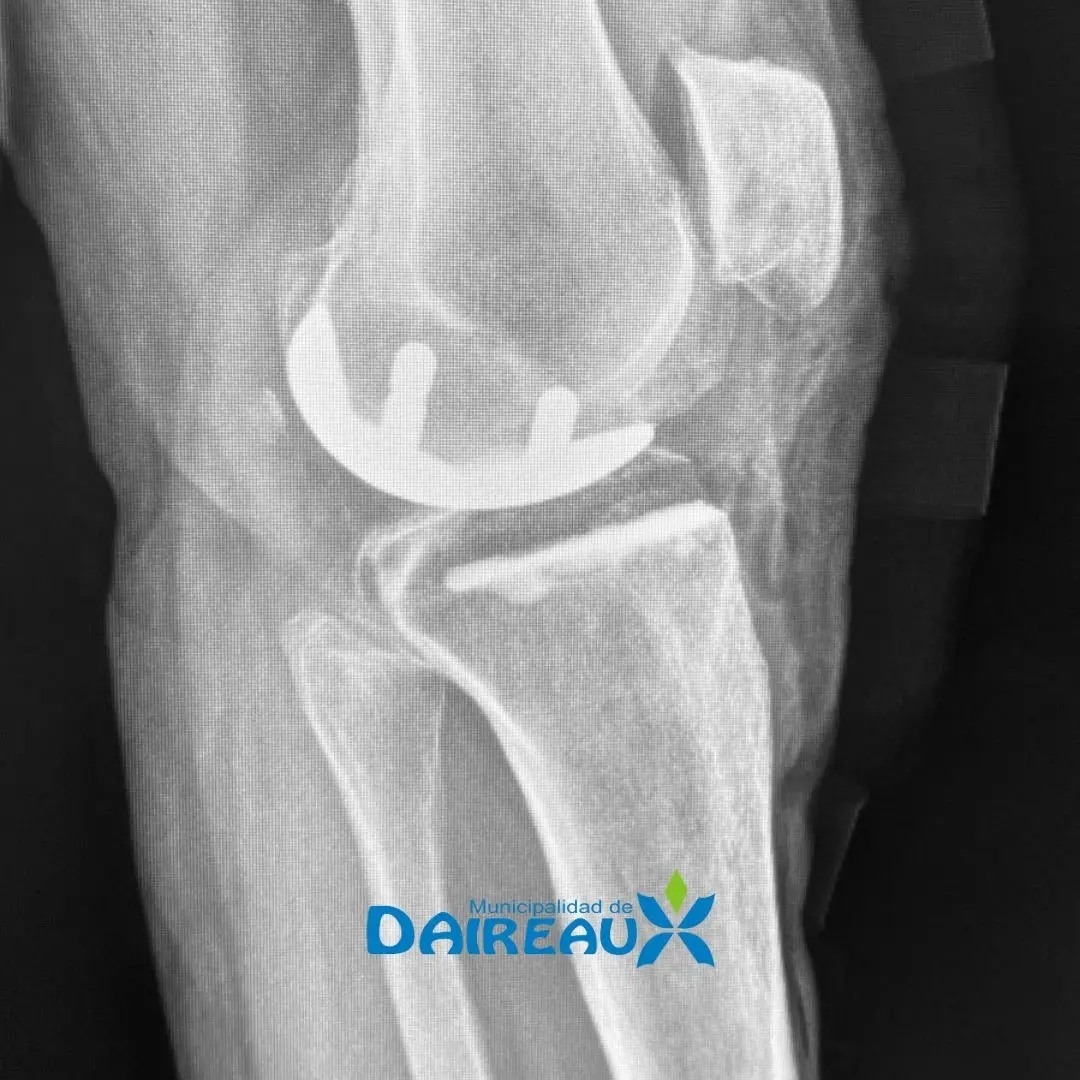

El médico lamatritense Juan Barrios participó recientemente de una innovadora operación de rodillas. Lo hizo como especialista en una intervención quirúrgica en Olavarría y también en el Hospital "Dr Pedro M. Romanazzi" de  Daireaux, en ambos casos a los pacientes se les realizó el reemplazo parcial o unicompartimental de rodilla.

“En las prótesis totales de rodilla se reemplaza la totalidad del hueso, en la unicompartimental solo se hace uno parcial. Estas últimas son más demandantes técnicamente se reemplaza el compartimiento afectado únicamente, sea para la parte interna o la externa”, se explayó Barrios.

“Lo que se hace es reemplazar la parte del hueso gastada, es una prótesis muy chiquita”, explicó Juan Barrios. Este tipo de intervenciones le permite al paciente una recuperación más rápida y se recomienda en personas en los que tienen dolor y  otro tratamiento no los ayuda a superarlo.